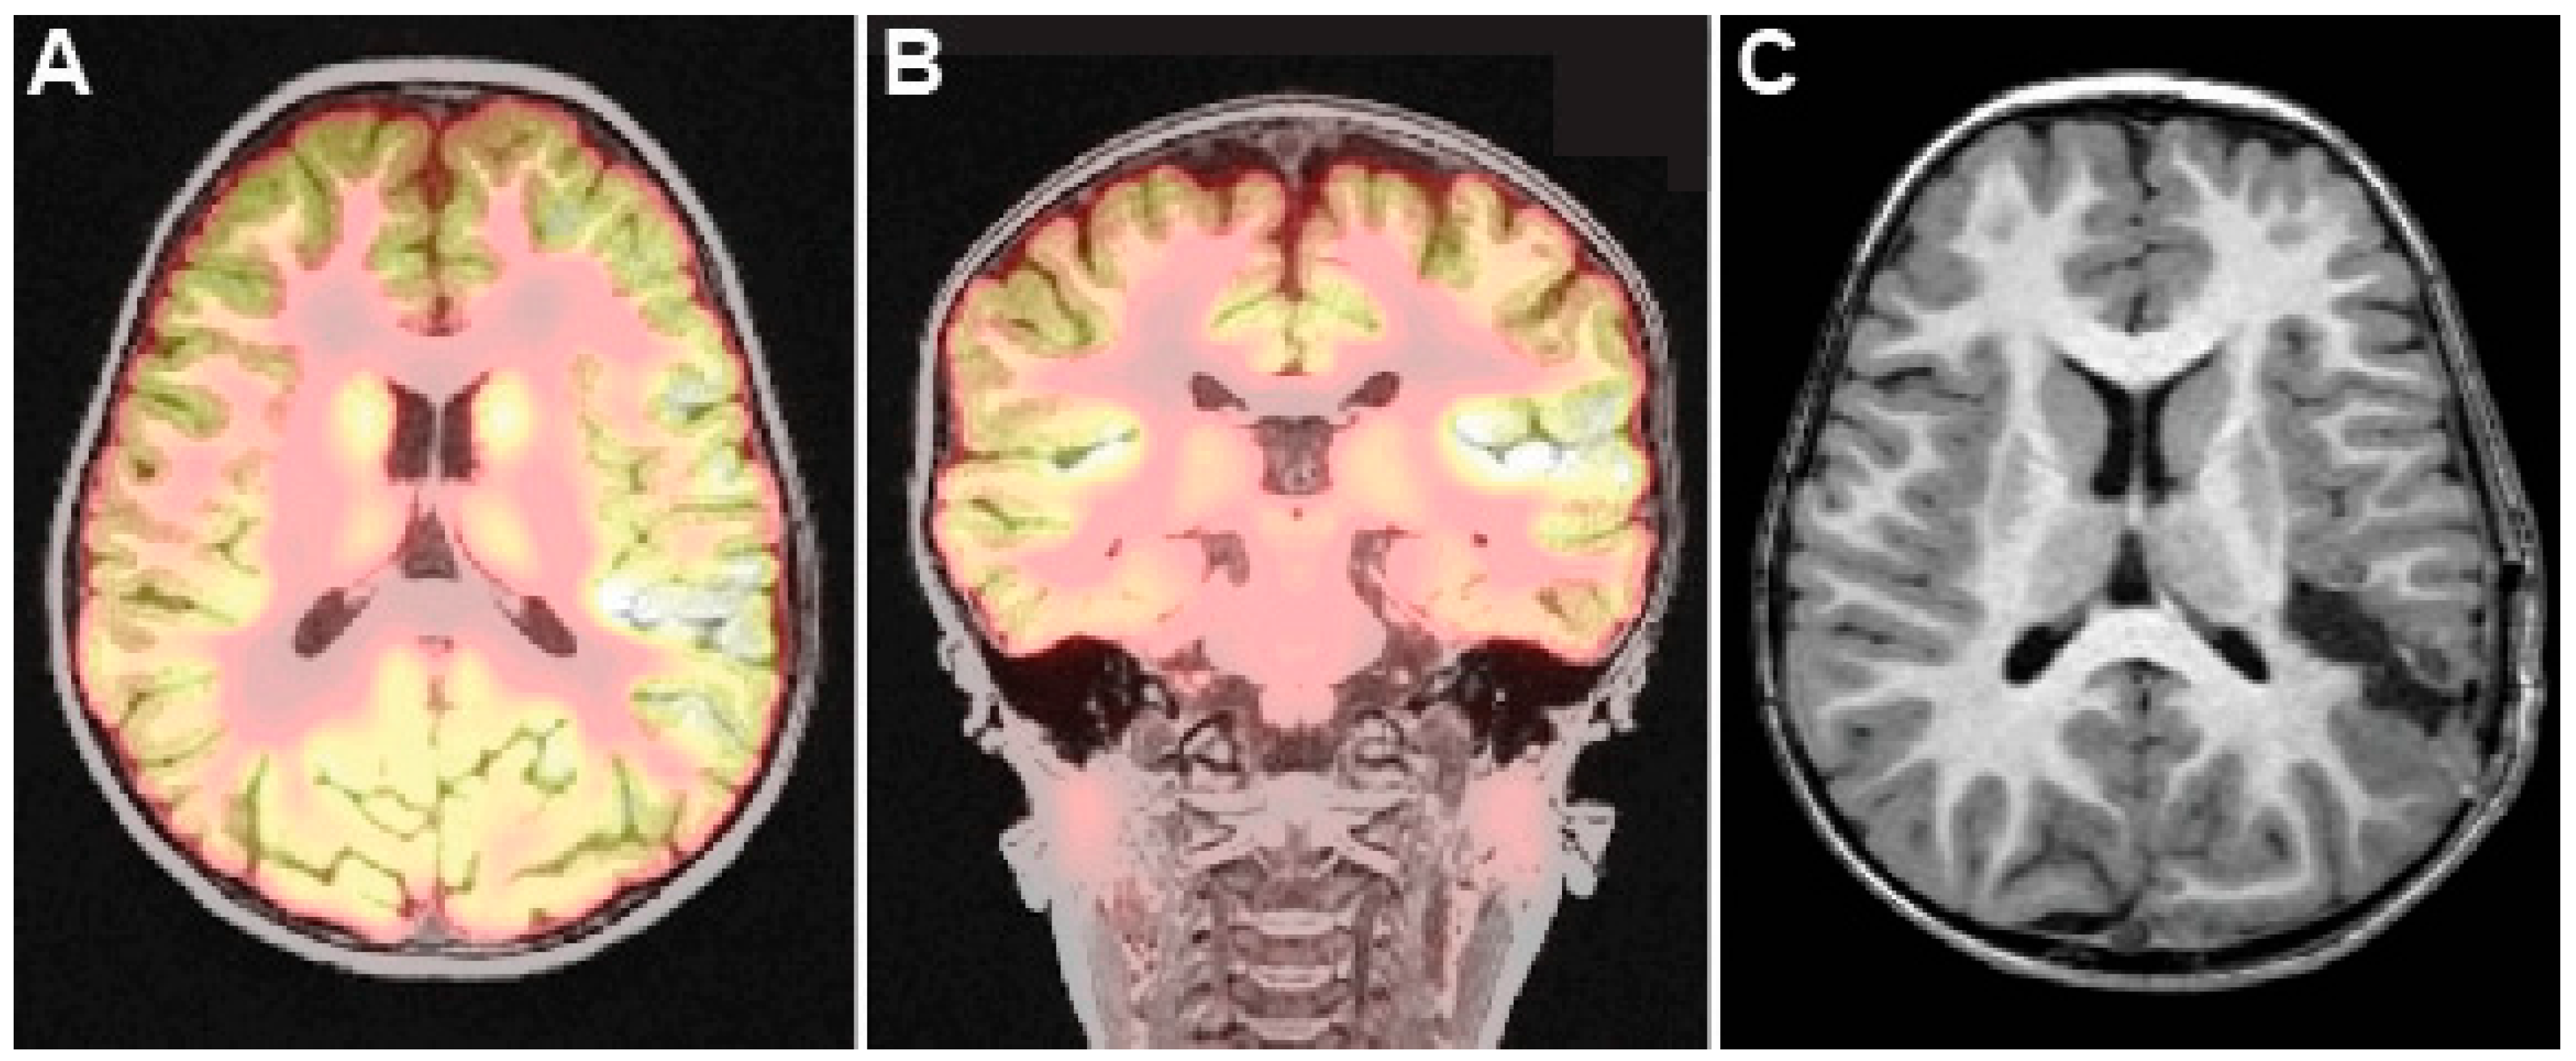

2.2. Case 2—Trans-Opercular Resection for Focal Cortical Dysplasia in the Left Superior Temporal Gyrus and Posterior Insula